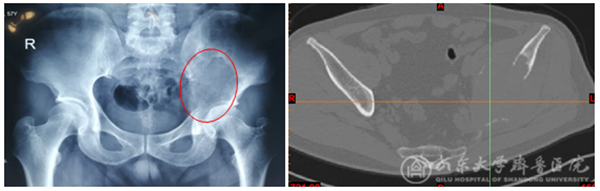

术前X线平片和CT可见肿瘤累及左侧髋臼及髂骨(1+2区),明显影响左髋关节的负重

患者是因为近几个月出现左髋部疼痛而就诊,检查发现左侧髋臼存在骨质破坏,鉴于患者在16年前做过肾癌的手术,全身的系统检查是必要的,除了局部骨盆的平片、CT和磁共振,全身的CT和骨扫描或者全身PET-CT也需要用于评估患者情况。通过系统检查,患者只有左侧骨盆一处病灶,这种情况需要进一步穿刺活检来明确病灶性质。10月14日,杨强主治医师在局麻下进行左骨盆肿瘤穿刺活检术,病理检查确诊为肾癌骨转移。在癌症家族中,肾癌相对较为特殊,容易发生骨转移,且肿瘤血运极为丰富,对放化疗和其他药物治疗相对不敏感,治疗较为棘手。对于单一病灶的肾癌骨转移患者,彻底的手术切除是临床指南所推荐的。病情明确后,经过医患沟通,确定治疗方案为彻底切除左骨盆肿瘤。